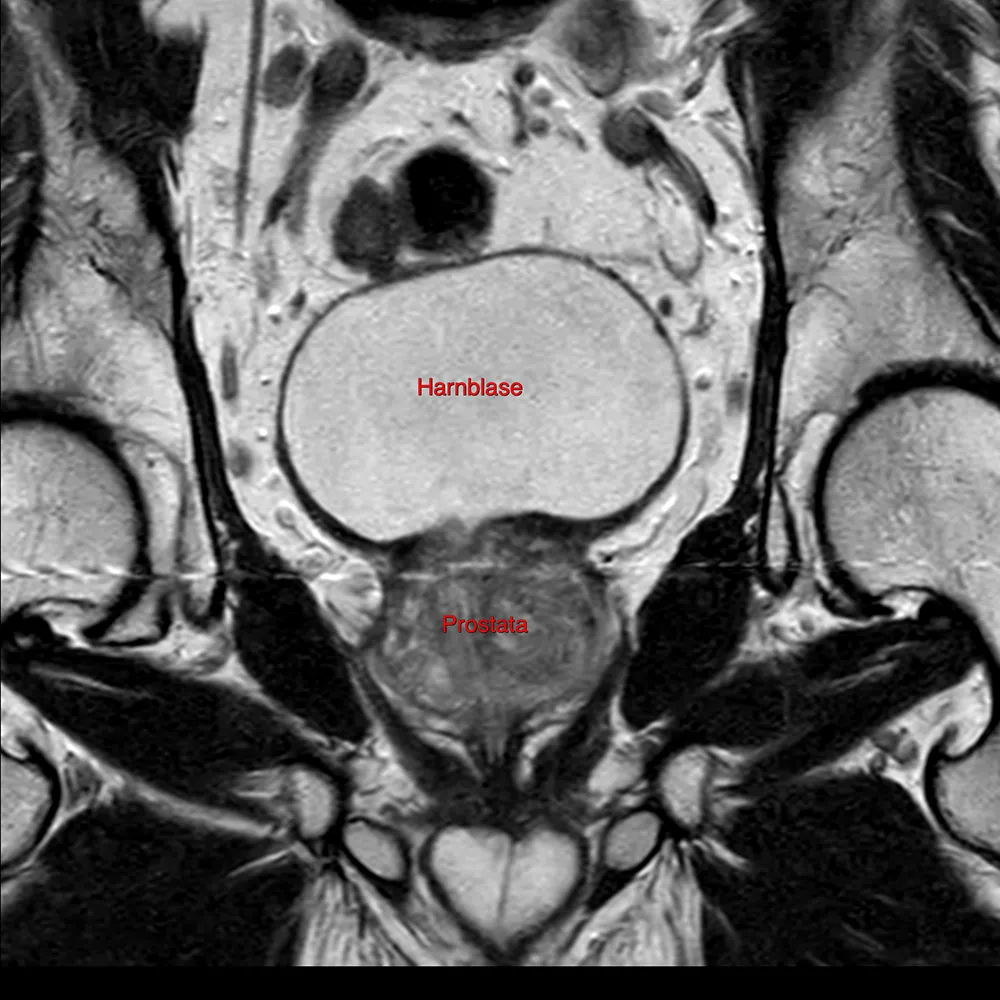

Das Prostata-MRT ist eine spezielle Form der Magnetresonanztomographie, bei der hochauflösende Bilder der Prostata und des angrenzenden Gewebes erstellt werden. Es handelt sich um eine nicht invasive Methode, die ohne den Einsatz von Röntgenstrahlen auskommt. Im Vergleich zu anderen bildgebenden Verfahren, wie der transrektalen Ultraschalluntersuchung oder der Prostatabiopsie, bietet das Prostata-MRT eine exzellente Bildqualität und eine besonders präzise Darstellung der Gewebestruktur.

Das Prostata-MRT liefert wichtige Informationen, die es ermöglichen, sowohl Tumore als auch andere pathologische Veränderungen im Gewebe frühzeitig zu erkennen. Gerade in den Anfangsstadien von Prostatakrebs, in denen noch keine Symptome auftreten, kann das MRT potenziell auffällige Stellen sichtbar machen, die ansonsten unentdeckt bleiben würden.

Bessere Behandlungsplanung: Sollte Verdacht auf Prostatakrebs bestehen, liefert das Prostata-MRT wichtige Informationen über die Größe, Lage und Ausbreitung des Tumors. Dies hilft den Ärzten, eine maßgeschneiderte Therapie zu planen, sei es in Form einer Operation, Strahlentherapie oder einer anderen Behandlungsmethode.

Auch für Männer, bei denen der PSA-Wert erhöht ist oder bei denen bei der digitalen rektalen Untersuchung Unregelmäßigkeiten festgestellt wurden, ist das Prostata-MRT eine wertvolle diagnostische Ergänzung. In Fällen, in denen eine Biopsie erforderlich erscheint, ermöglicht das MRT eine präzisere Zielgenauigkeit, indem es die genaue Lokalisation des verdächtigten Gewebes anzeigt.